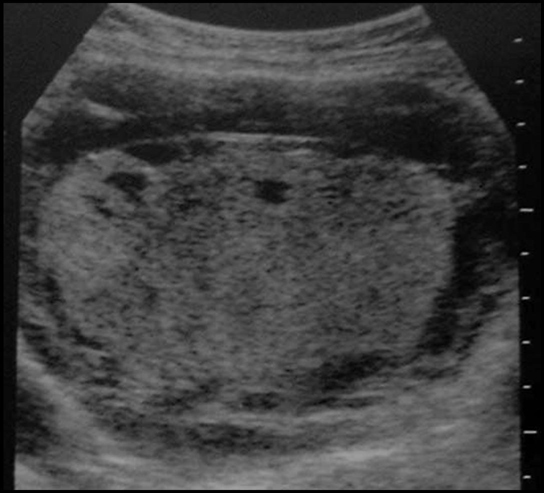

Cancer de l’endomètre.

Envahissement du myomètre

Diminution de l’épaisseur du

myomètre en regard de la lésion par rapport au myomètre

à distance